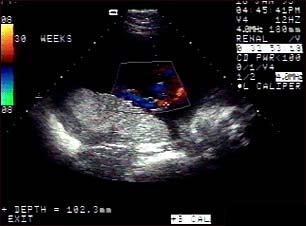

Ecografia fetala